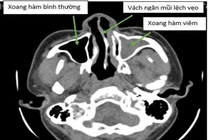

Bệnh nhân được tư vấn đeo máy trợ thở nhưng bệnh nhân không áp dụng được vì khá bất tiện. Nội soi khi ngủ xác định hẹp ở vùng màn hầu và amidan sau đó quyết định phẫu thuật cắt màn hầu và amidan và thu nhỏ cuốn mũi vì bệnh nhân bị viêm mũi dị ứng và thường xuyên ngạt”, BS Đào Đình Thi, Trưởng khoa Nội soi - Bệnh viện Tai Mũi Họng Trung ương cho biết về tình trạng của bệnh nhân.

Sau khi được thăm khám bằng 3 phương pháp, các bác sĩ Đào Đình Thi, Trưởng khoa Nội soi- Bệnh viện Tai Mũi Họng Trung ương và các cộng sự tại bệnh viện Tai Mũi Họng Trung ương đã xác định được một số điểm hẹp và mức độ ngưng thở khi ngủ của bệnh nhân Bùi Xuân Mạnh.